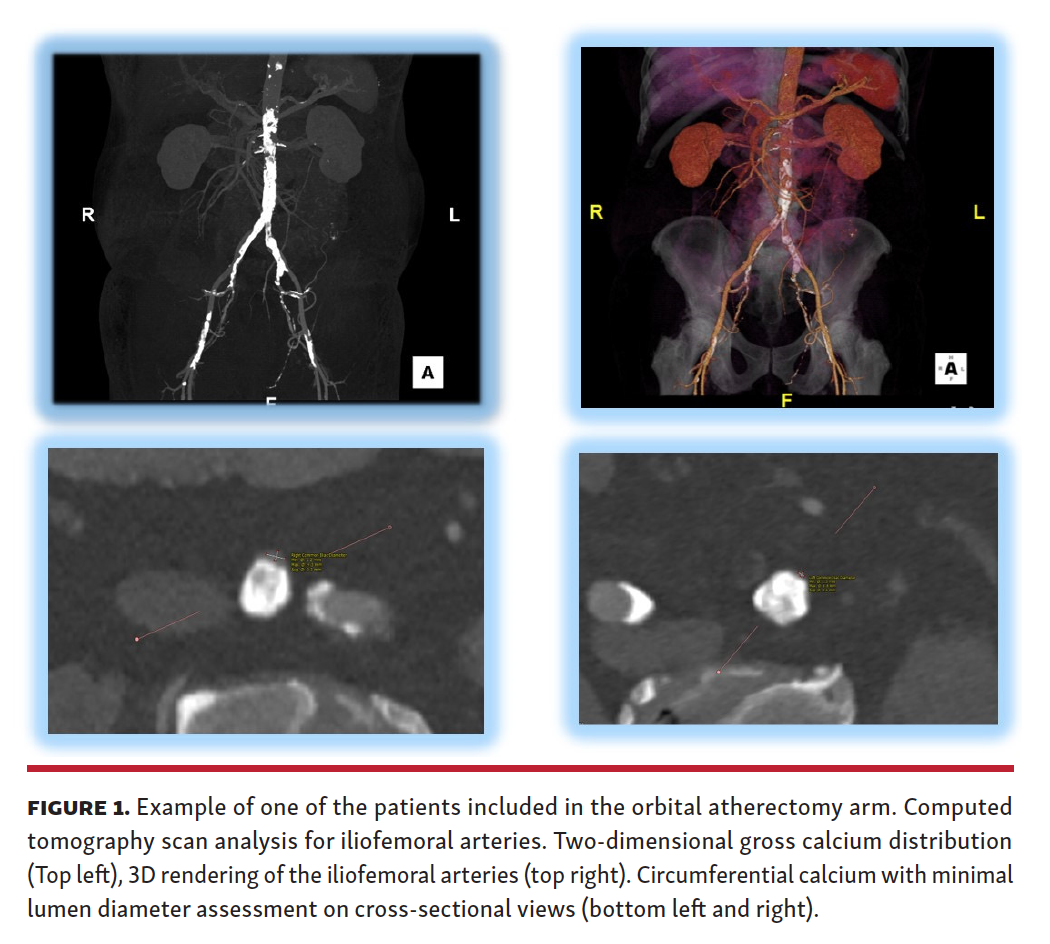

CT review. All CT scans were analyzed using a dedicated workstation (3Mensio Valves Software, Pie Medical Imaging) at the interventional site from the common femoral artery (CFA) to the distal aorta. The following measurements were obtained: minimal lumen diameter (MLD); maximum luminal diameter; vessel area at the site of the most severe narrowing; degree of vessel calcification; and tortuosity. The mean lumen diameter was computed as the average vessel diameter (maximal + minimal diameter/2), measured at the MLD. Calcification was defined as severe if an arch >270° was present (Figure 1).